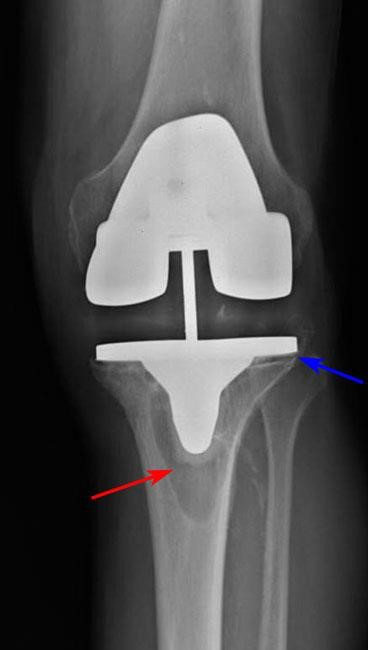

Osteolysis (red arrow) has occurred around the tibial component, causing it to become loosened from the bone (blue arrow).

The cause of loosening is not always clear, but high-impact activities, excessive body weight, and wear of the plastic spacer between the two metal components of the implant are all factors that may contribute. Patients who are younger when they undergo the initial knee replacement may "outlive" the life expectancy of their artificial knee, and there is a higher long-term risk that revision surgery will be needed due to loosening or wear. In some cases, tiny particles that wear off the plastic tibial spacer accumulate around the joint and are attacked by the body's immune system. This immune response also attacks the healthy bone around the implant, leading to a condition called osteolysis. In osteolysis, the bone around the implant deteriorates, making the implant loose or mechanically unstable.